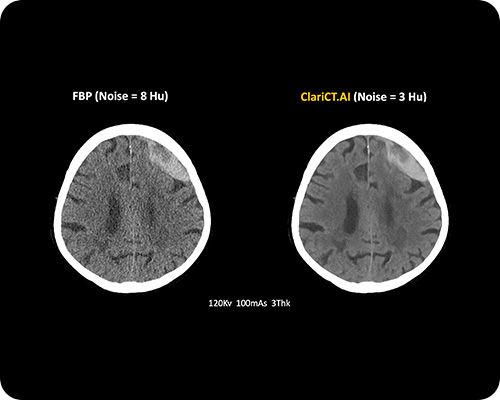

ClariCT.AI

AI-Powered Radiation Reduction

The first AI software that dramatically reduces radiation exposure while delivering the highest quality CT images using advanced AI denoising technology.

Reduces radiation exposure by 70-95% while maintaining superior image quality